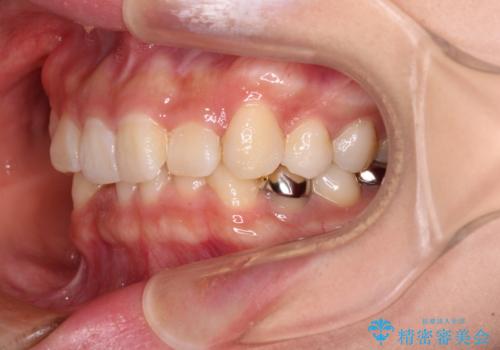

- 前歯のデコボコと深い咬み込みを気にして来院された患者様です。

インビザラインを用いて、前歯の叢生を解消するとともに、深い咬み合わせ(ディープバイト)を改善していくこととしました。

奥歯を後方に直立させることで深い咬み合わせを改善を図り、隠れていた下顎前歯が見えるほどになりました。